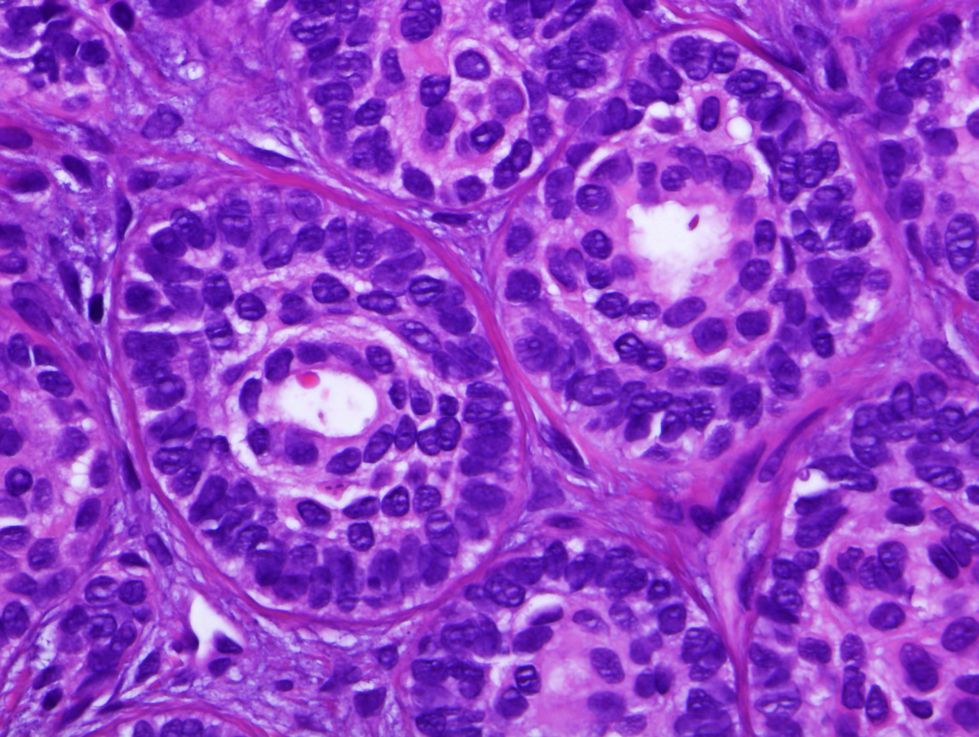

Cas dermatopatologia. Què és el nuvolet que apareix al logo d'ADA?

Febrer 2013

Ho saps?